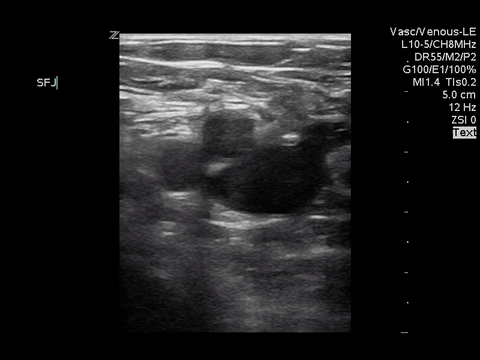

We can eliminate a few diagnoses off the differential with this scan. However, with the diagnosis of PE remaining a 2-point DVT scan was carried out:

Right lower extremity

In each of these images it appears the vein fully collapses with compression. We can conclude that there is likely no DVT present within the limitations of the 2-point compression scan (see discussion for further details)